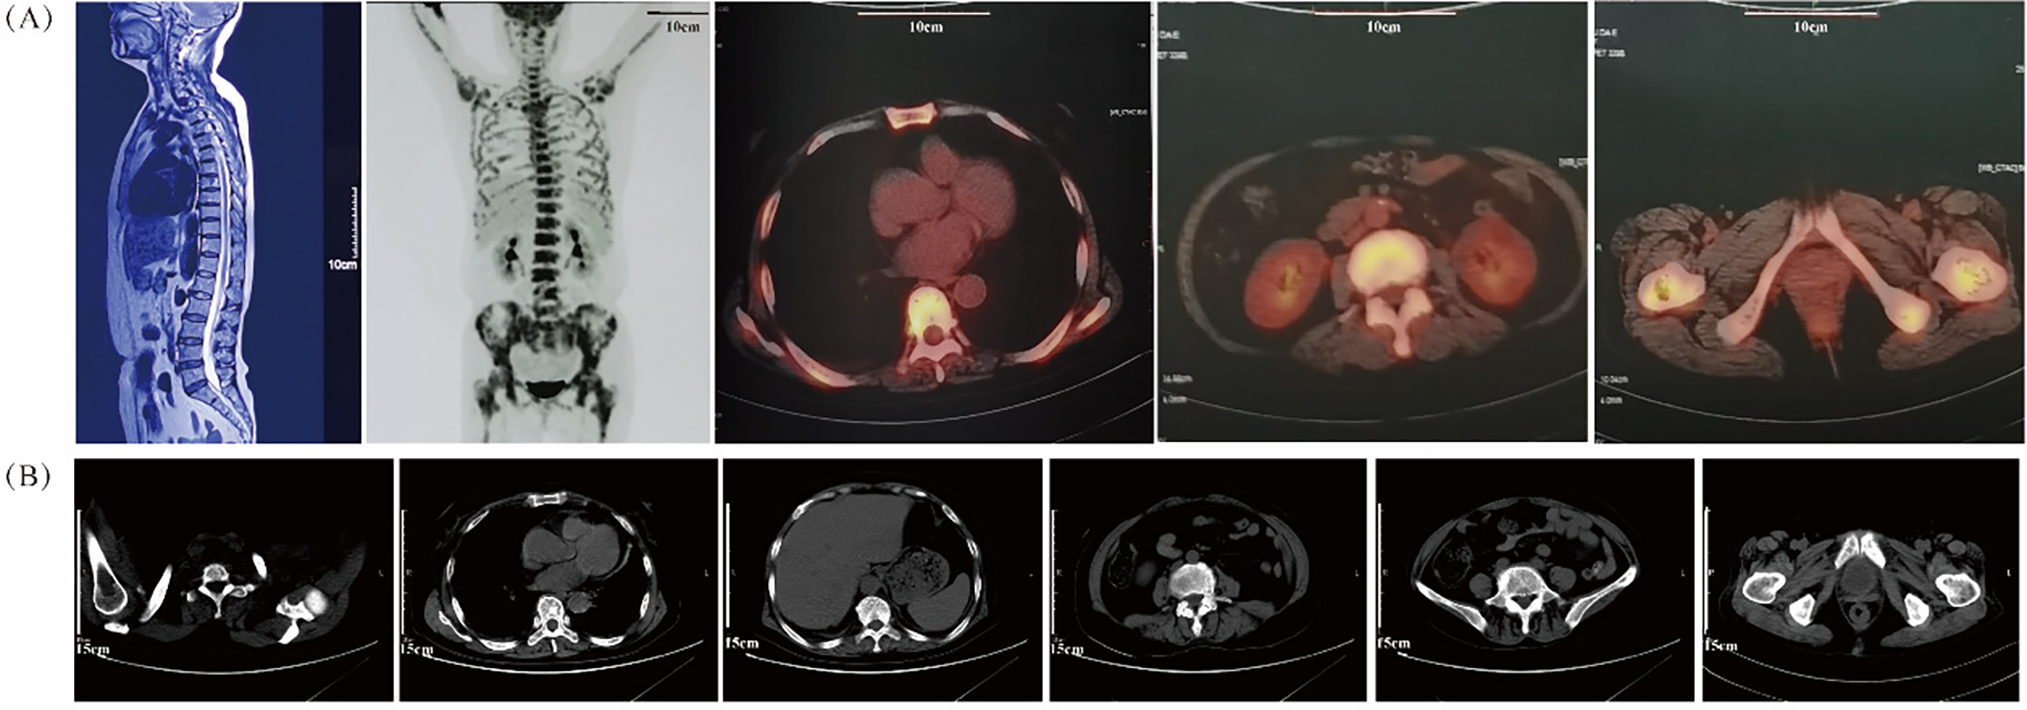

Upon physical examination, there were no signs of swelling in the left hip or enlargement of superficial lymph nodes. Magnetic resonance imaging (MRI) revealed multiple abnormal diffuse signals in the pelvis, thoracic and lumbar vertebrae, with local cortical destruction in the femoral heads and bilateral iliac bone. Fluorine-18-fluorodeoxyglucose (18F-FDG) positron emission tomography-computed tomography (PET-CT) showed diffuse increased 18F-FDG uptake in the bone marrow (SUVmax 9.2), without evidence of bone tumors, liver, spleen, or lymph node involvement (Fig. 1A). Subsequent bone marrow smear indicated active proliferation, and flow cytometry revealed no obvious abnormal cells, although most of the laboratory examination results were not available. She was then treated with analgesics and experienced short-term relief of symptoms.

Figure 1: Radiologic results by MRI, PET/CT and CT scans. (A) The MRI image (left panel) shows multiple abnormal bone signals in the vertebral column. The PET/CT images (right four panels) reveal extensive uptake of bone marrow without evidence of involvement in the liver, spleen, or lymph nodes; (B) The plain CT scans before treatment do not show any evident bone lesions

On 01 December 2020, the patient presented to our cancer center with worsening fatigue, night sweats, and pain in both the lower back and left hip. Physical examination revealed new signs of anemia but no jaundice, hepatosplenomegaly, or lymphadenopathy. Plain CT scanning did not show any obvious bone lesions (Fig. 1B). Initial hematologic evaluation demonstrated pancytopenia with leukopenia (WBC 2.1 × 109/L; reference 4.0–10.0 × 109/L), neutropenia (1.40 × 109/L; reference 2.04–7.5 × 109/L), and severe anemia (Hb 68 g/L; reference 110–150 g/L) with erythrocytopenia (RBC 2.40 × 1012/L; reference 3.5–5.0 × 1012/L). Thrombocytes remained normal (218 × 109/L; reference 100–300 × 109/L). Marked inflammatory activity was evidenced by elevated CRP (103.4 mg/L; reference <8.0 mg/L) and ESR (151 mm/h; reference 0–20 mm/h). Metabolic disturbances included increased LDH (329 U/L; reference 120–246 U/L) and ALP (242 U/L; reference 45–129 U/L), with marginally raised β2-microglobulin (1.6 mg/L; reference 0.9–2.7 mg/L). Immunologic studies revealed monoclonal IgA-λ paraproteinemia without Bence-Jones proteinuria.